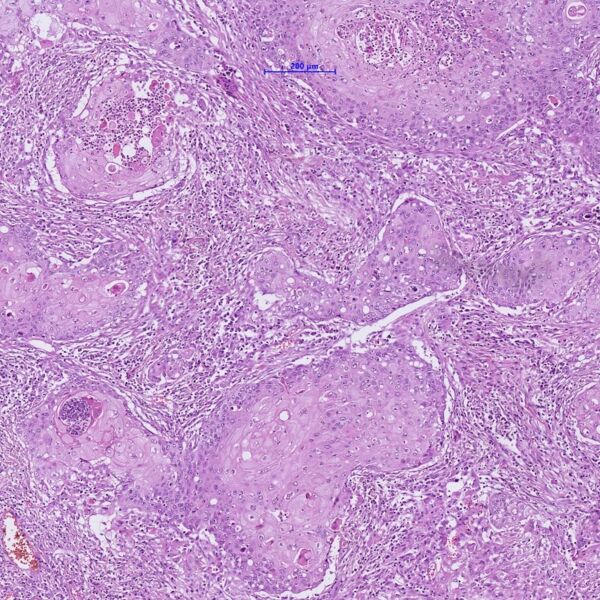

Lungentumor: Mikroskopische Aufnahme einer Gewebeprobe aus einem Lungentumor. Die vielen dicht beieinanderliegenden atypischen Zellen zeigen, dass es sich um ein Karzinom handelt.